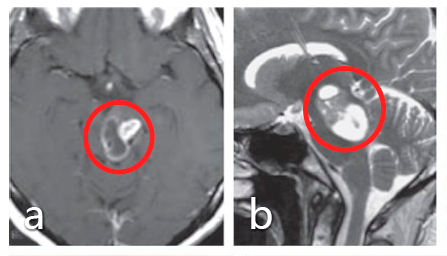

基本情況:30歲女士,有復視和輕微右側(cè)偏癱 術(shù)前:a、b圖患者術(shù)前MRI顯示中腦腫瘤,患者較初接受立體定向囊腫抽吸和間質(zhì)放療,并被診斷為毛細胞型星形細胞瘤,但腫瘤仍在生長。...

基本情況:30歲女士,有復視和輕微右側(cè)偏癱

術(shù)前:a、b圖患者術(shù)前MRI顯示中腦腫瘤,患者較初接受立體定向囊腫抽吸和間質(zhì)放療,并被診斷為毛細胞型星形細胞瘤,但腫瘤仍在生長。